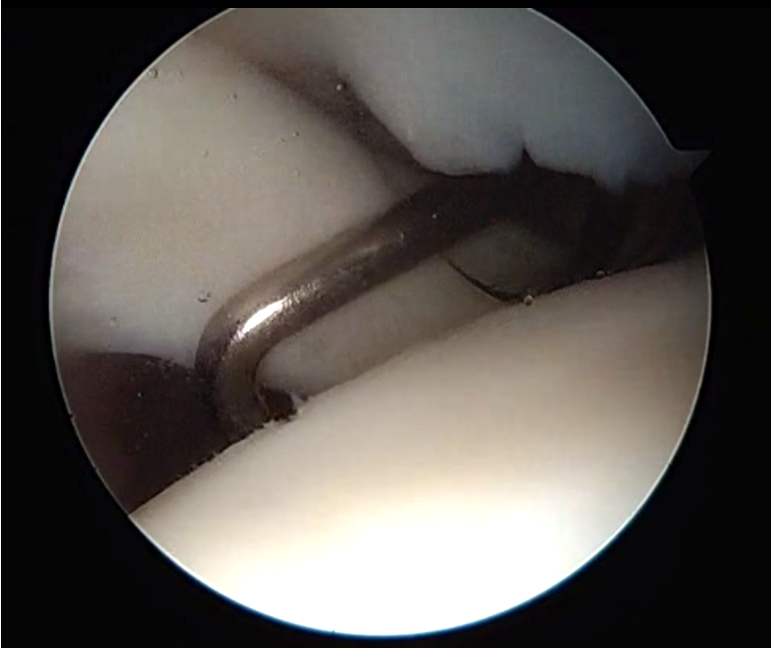

2. Retracted tendon tear

- tag and release biceps tendon

- lateral traction sutures in subscapularis

- extensive tendon release with cautery and recreate rotator interval

- repair as above

Lateral traction sutures placed in subscapularis, then cautery used to remove scar tissue and recreate rotator interval